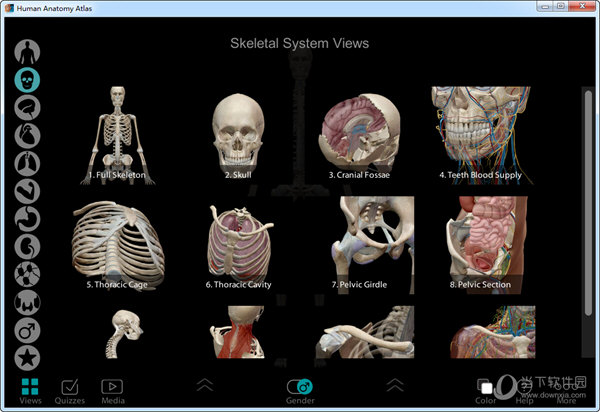

7、点击主界面的左上角VIEWS,可以进入各模块的查看,详细的分支让你更加了解人体构成。